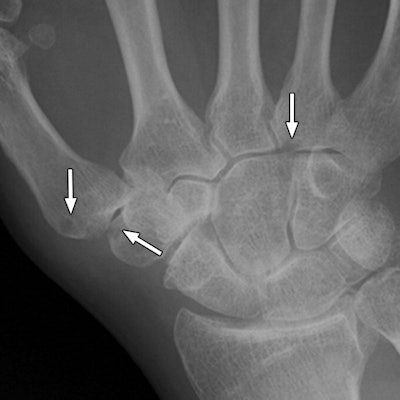

Images are of a 67-year-old man with rheumatoid arthritis. Bone erosion with significant overlapping of bones (arrows) can be difficult to evaluate on radiography (above), compared with tomosynthesis (below and bottom). Images courtesy of AJR.